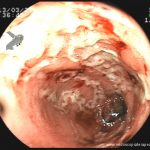

- Doença de Crohn em atividade – estenose se anastomose ileocolônica